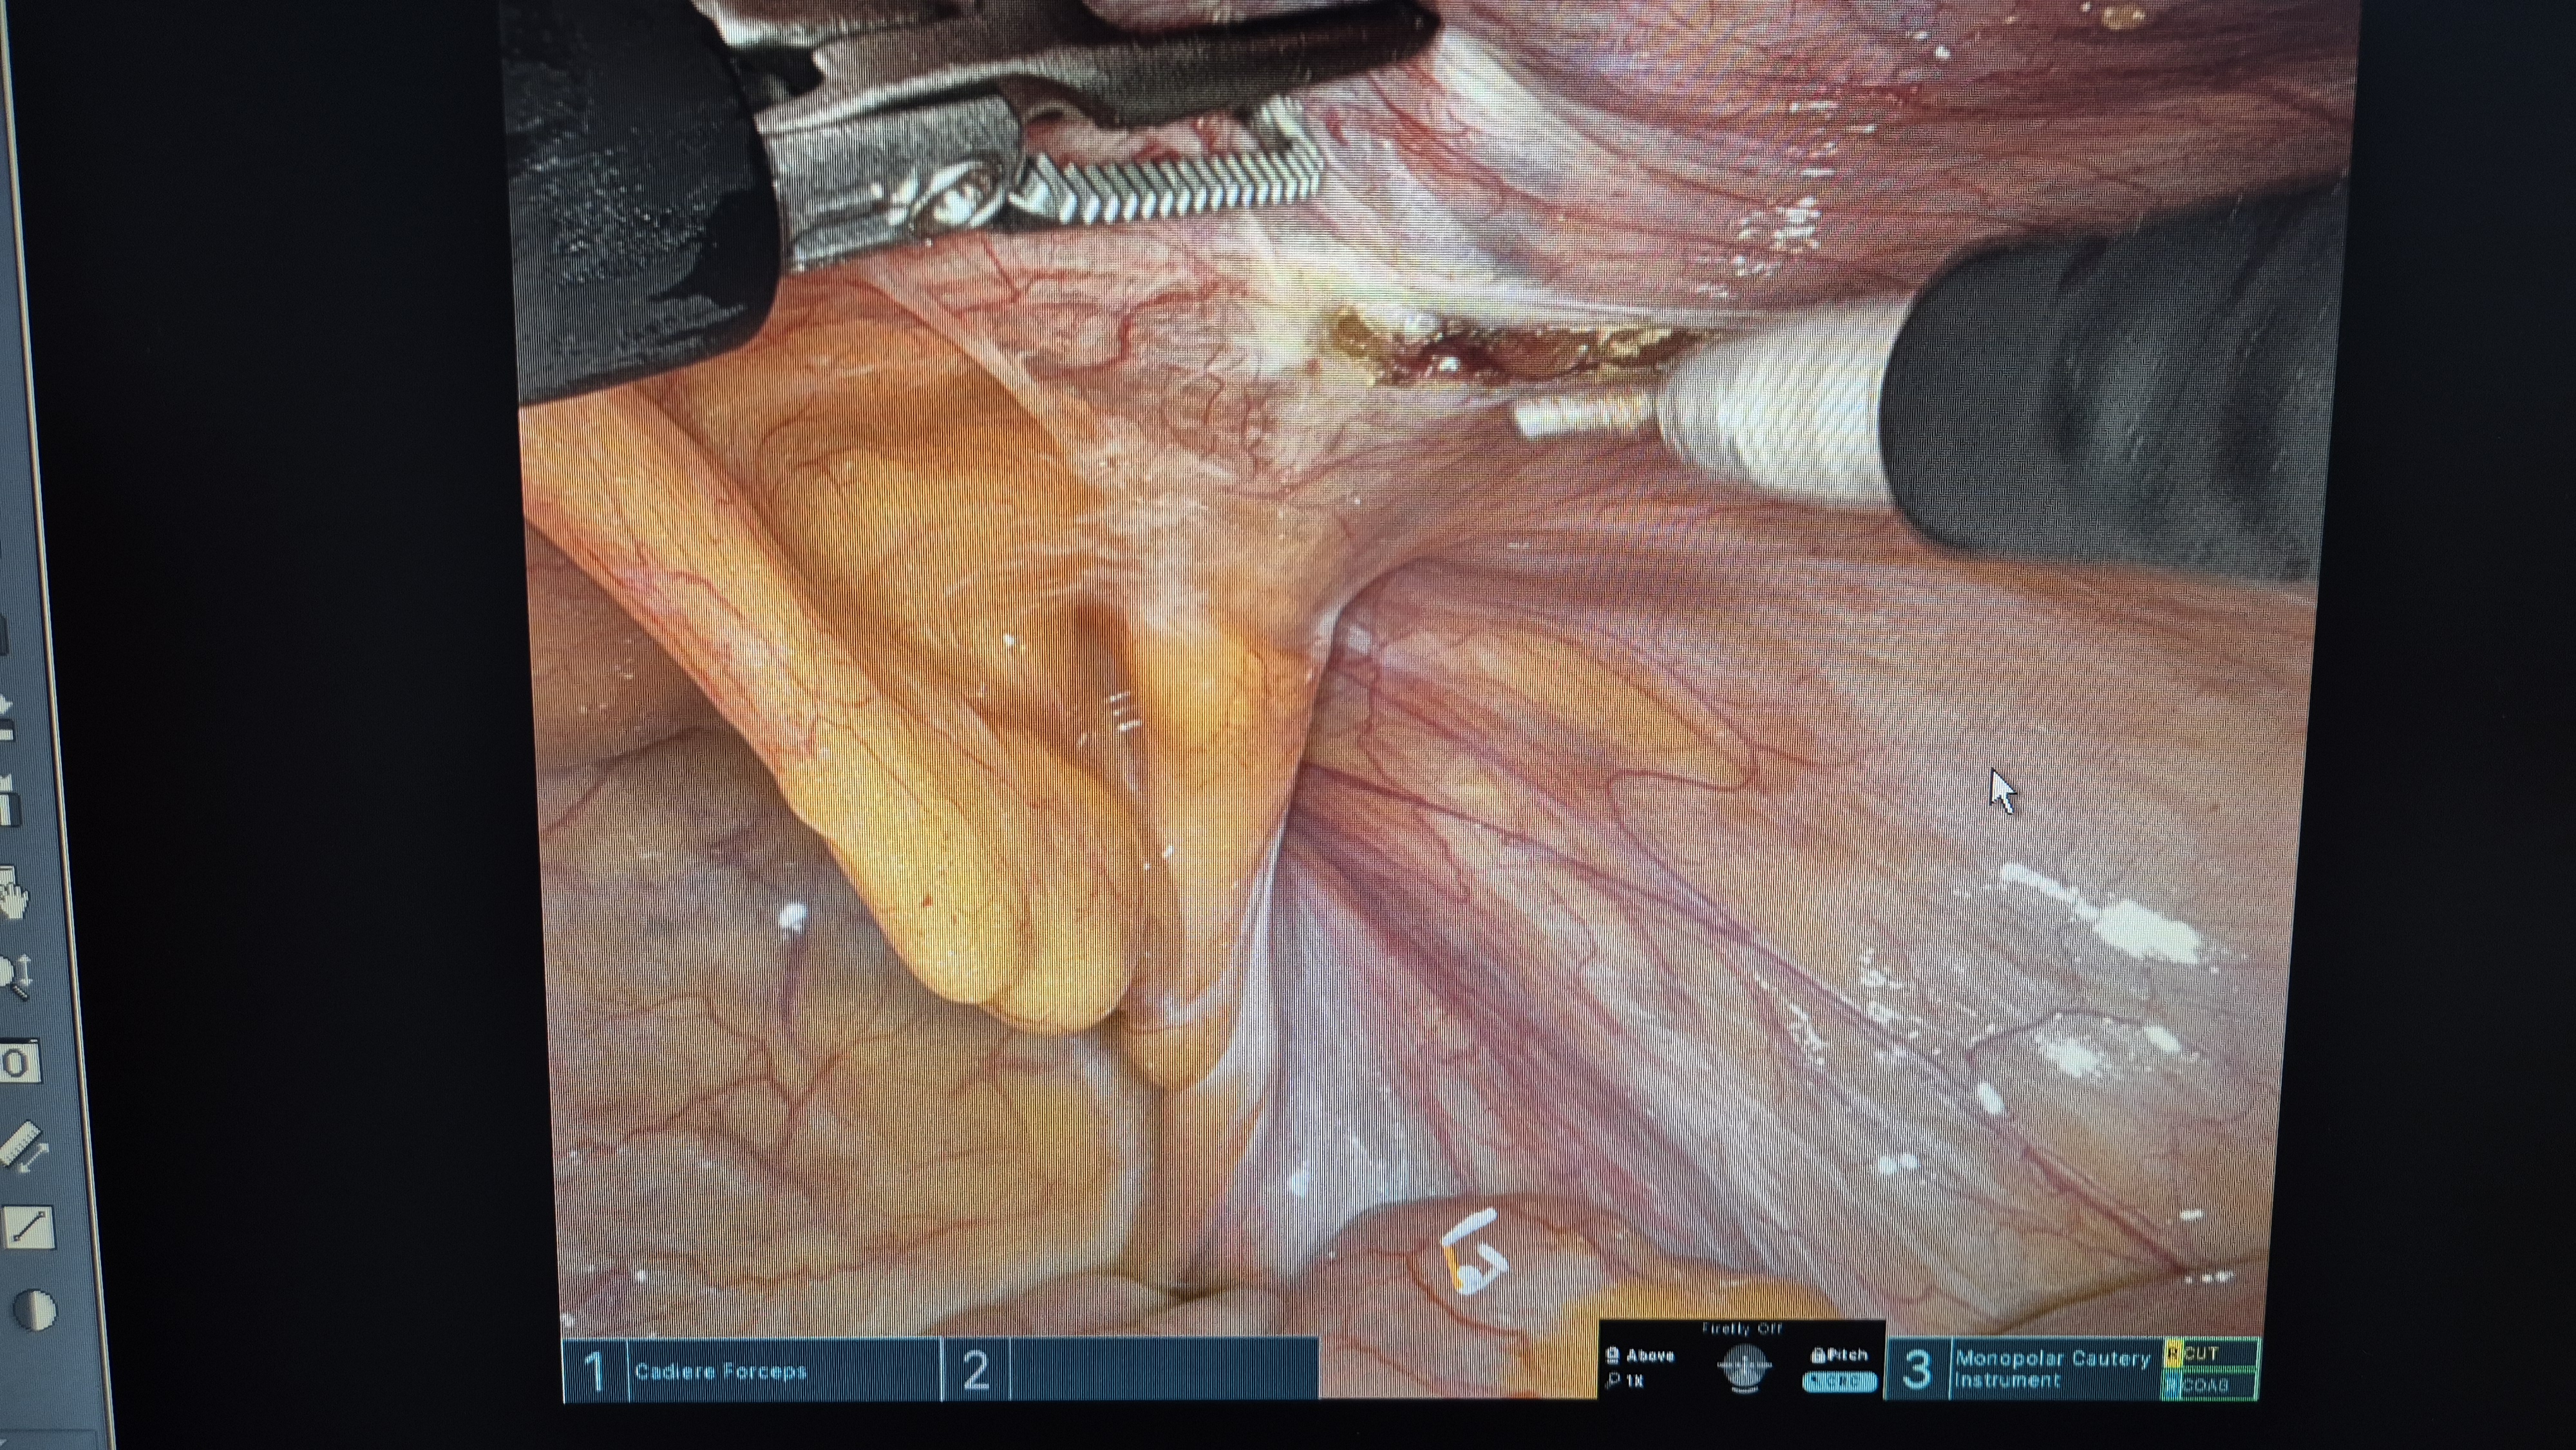

탈장 확인.

복막 열고.

박리.